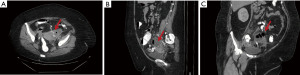

A CT scan with oral and rectal contrast was performed to better delineate the source of infection, assess bowel involvement, evaluate interval improvement after 48 hours of antibiotics, and determine whether percutaneous drainage remained unfeasible. This demonstrated no evidence of obstruction but revealed colonic diverticulosis and a stable complex cystic lesion in the left adnexa containing multiple air-fluid levels. A linear tract of rectal contrast extended from a colonic diverticulum to the adnexal collection, which contained a small amount of contrast (Figure 2).